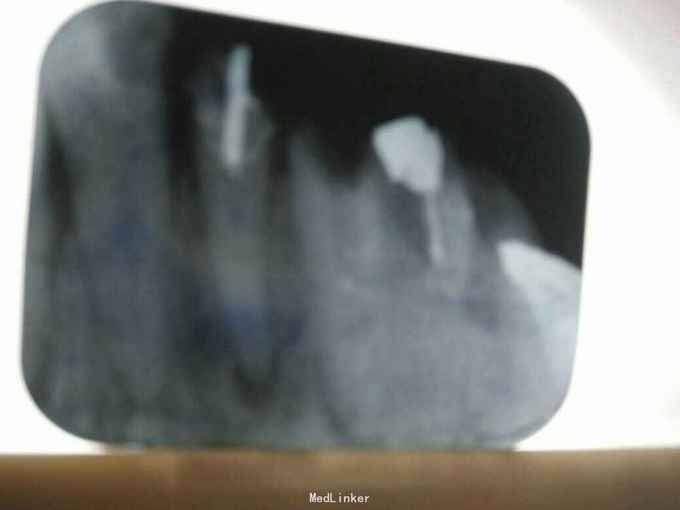

检查: 12-16可见冠修复体;12-15烤瓷冠;16金属冠;12,13连冠;14,15,16连冠;12,14,15頰侧根尖部有3个粟粒大小的乳头状牙龈窦道,挤之有脓液溢出,牙无明显松动,冷热诊无反应,叩(++),其余无异常 x线片示:12-15根尖部有形状不规则,边缘模糊的透射阴影区,14,16牙根内有高密度阻射物,14可腭根欠填 全口口腔卫生良,牙石I度,色素II度,软垢II度其余无异常

诊断: 12,13,14,15慢性根尖周炎(根尖周脓肿) 治疗计划: 1. 拆冠 2. 12,13,15 行rct+桩(拆冠后:12去軟龋后可见根管钉,13残根;12纤维桩,13铸造桩) 3. 14根管再治疗 4. 12,13连冠修复,14,15,16连冠修复 诊断依据:患牙死髄牙,根尖有龈窦,更主要是x线片示根尖部有形状不规则,边缘模糊的透射阴影区